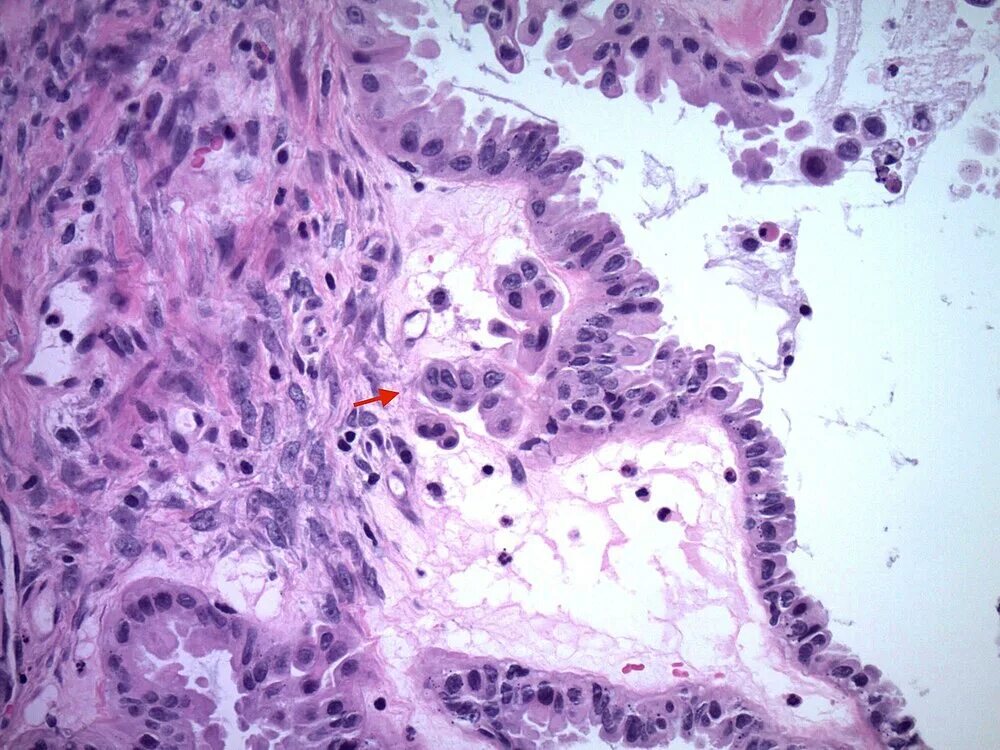

Гистология фото